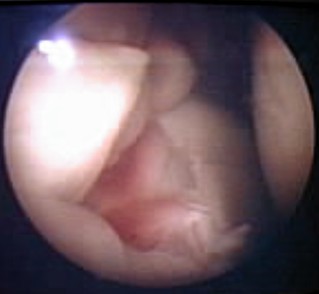

Artritis Idiopática Juvenil, visión artroscópica (4/11)

Engrosamiento de la membrana sinovial con enrojecimiento por aumento de la vascularización en fase inicial Cortesía de la Dra. Dolores Cantera Oceguera cantera@infomed.sld.cu